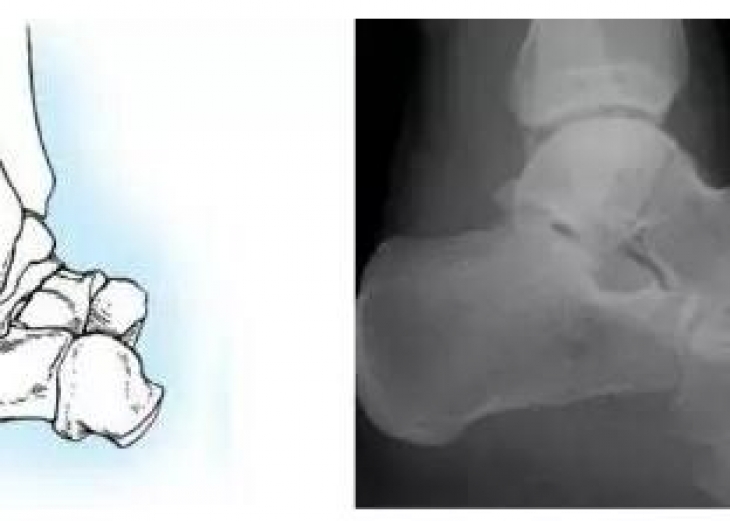

距骨是连接下肢和足部的枢纽,肩负重力传递和运动的耦联,是足部重要的功能单位。距骨骨折按部位分为距骨头骨折、距骨颈骨折、距骨体骨折和距骨周围突骨折。距骨颈骨折占距骨骨折的50%~80%,是临...

踝关节是人体负重最大的关节,由3块骨骼和11条韧带组成。急性踝关节损伤在临床常见,其中踝关节外侧副韧带损伤是全身最常见的韧带损伤,而踝关节骨折居关节内骨折之首。美国国家创伤数据库资料显...